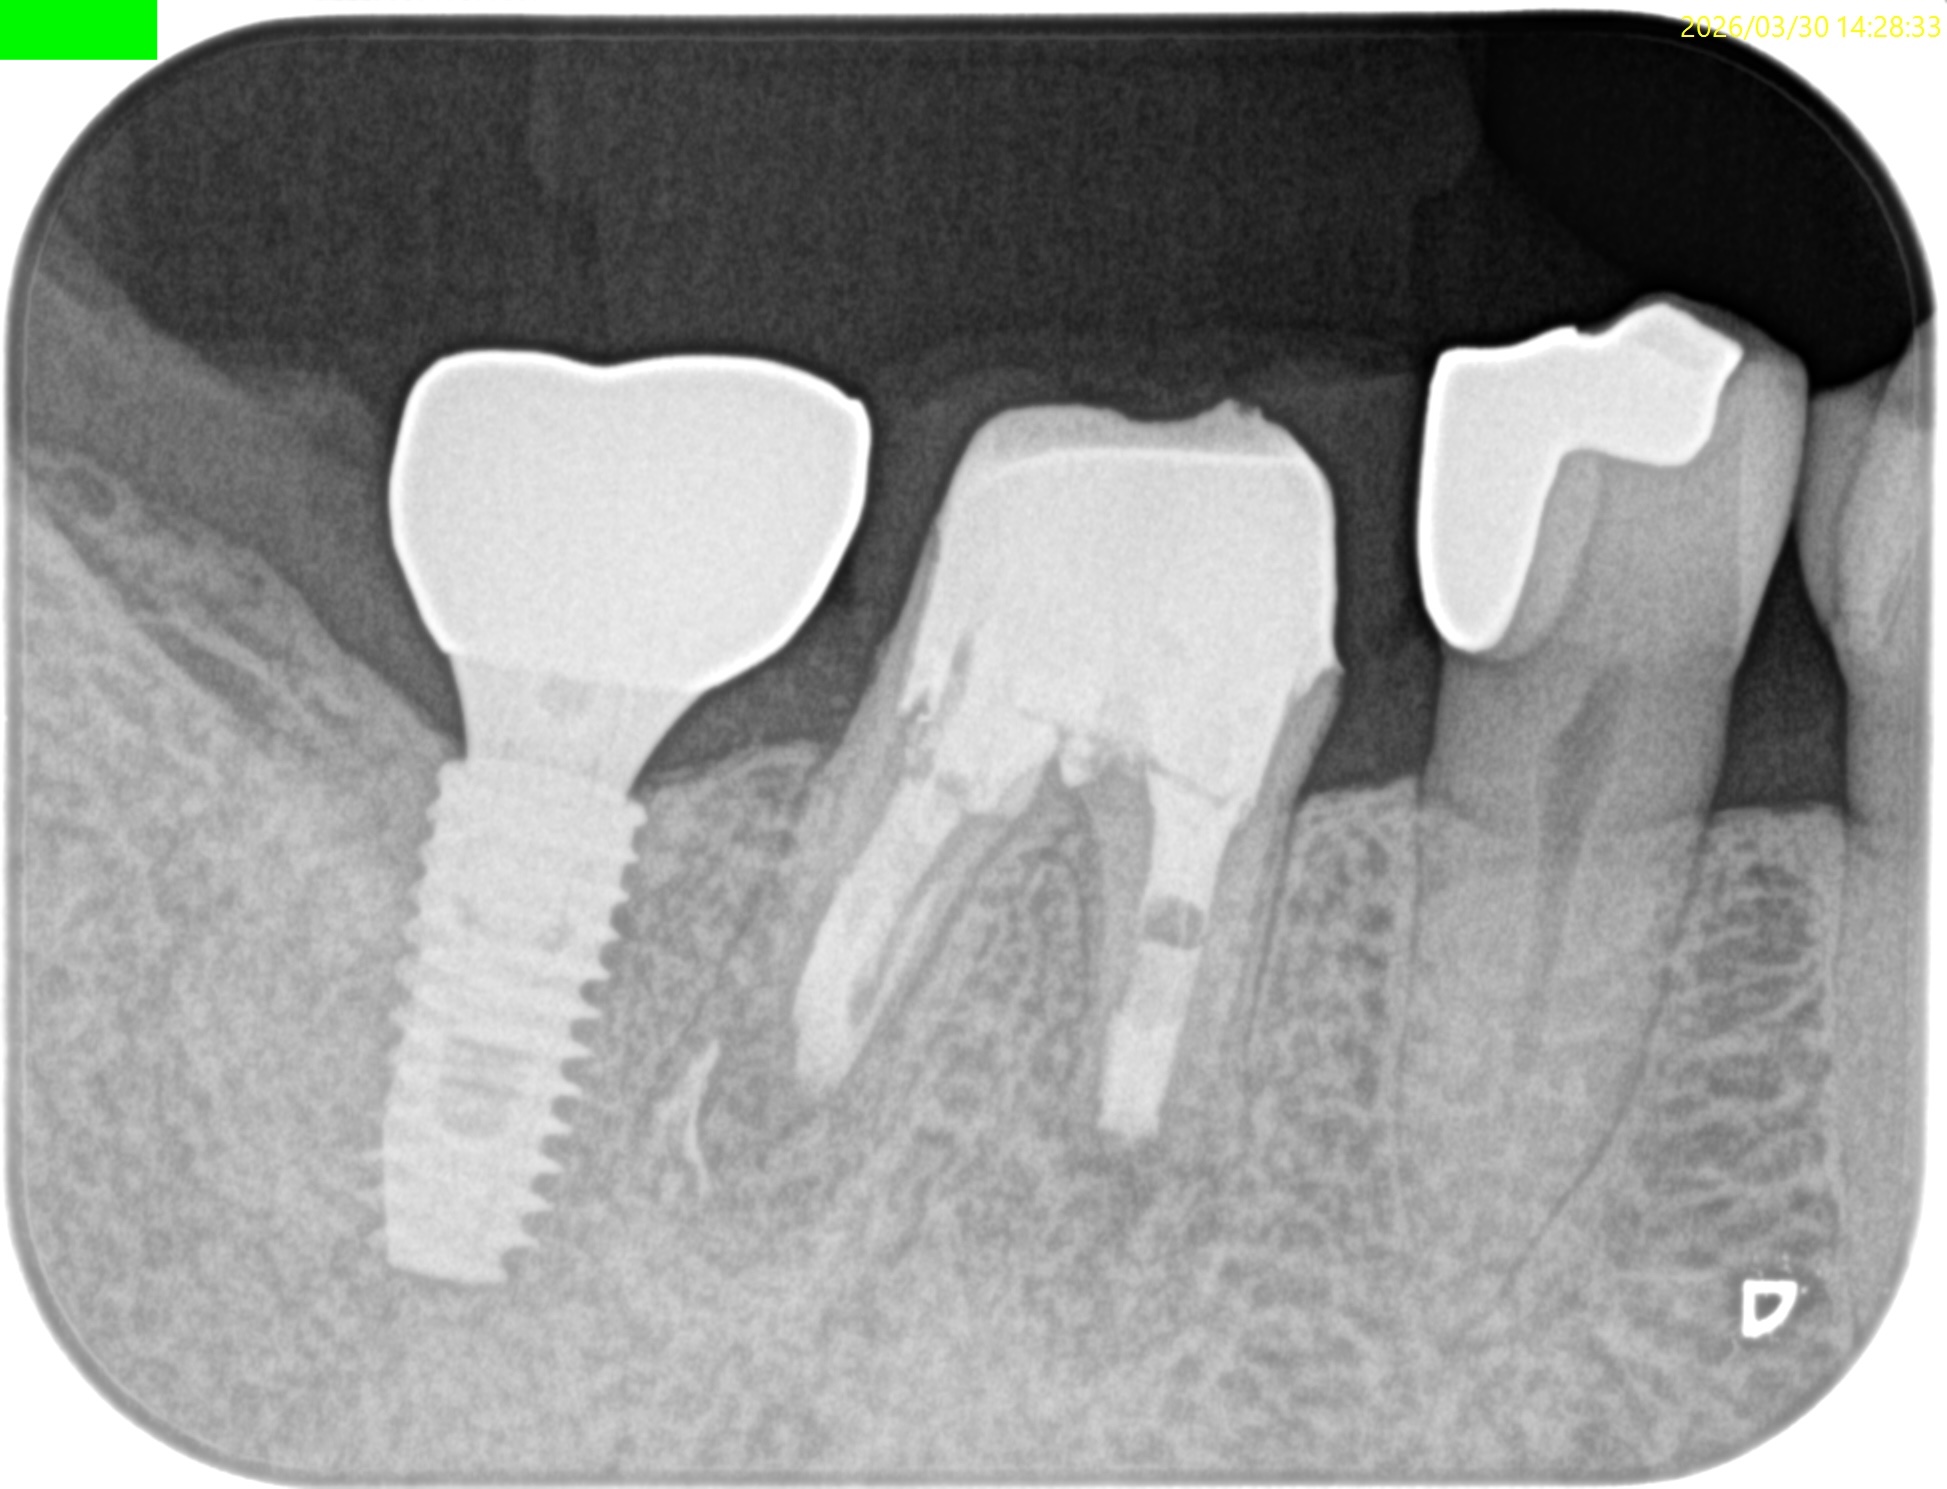

#30 M,D Apicoectomy 5M recall(2026.3.30)

M

外科直後と比較した。

最終補綴もOKだ。